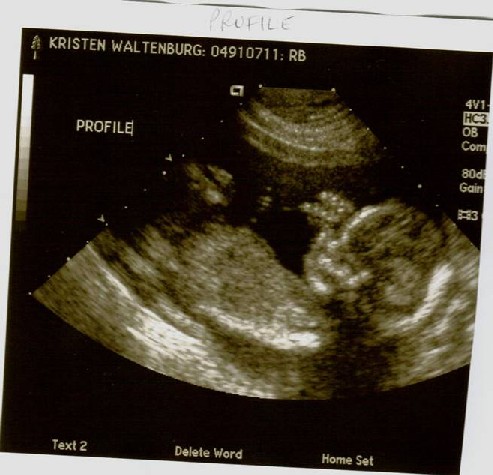

After following a strict schedule of how much water to drink, when to drink it, when to pee and when not to pee, Colby and I arrived at Kaiser for our big ultrasound appointment! The BIG day, when we would find out if we have a pink or blue bun in the oven!! While pacing up and down the aisle in a desperate attempt to stay in control of my bladder, my mom, Colby’s mom and his sisters join us for the long awaited peek. Finally! My name is called and I’m provided some relief as I lie down on the chair in the dark room. The nurse squirts some gel on my belly, which I was grateful to realize they warm it on this floor! She proceeds with the ultrasound, taking pictures for the doctor for about 20 minutes. I didn’t get a peek until the others were invited in. We saw distinct hands and feet, a big alien head, even an ear… but what we really wanted to see was obstructed by two little legs, crossed at the ankles. No angle could seem to enlighten us!! So, the nurse admitted that when she was taking pictures on her own, she got a possible view of what she thinks are boy parts, but since she couldn’t get back under there to verify it, she said she would print that picture and leave it to our interpretation. That’s where you come in. Please take a look at the pictures below. The one labeled “Gender” is the deciding factor. Once you’ve gotten a good look, please use the “post your comment” link at the bottom of this blog, and let us know if you believe it to be a boy or girl. Profile:

Alien Face: